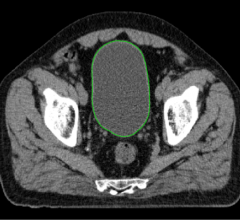

October 25, 2020 —Philips, a global leader in health technology, will showcase its latest advances in radiation oncology ...

October 24, 2020 — An estimated 1.8 million new cancer cases will be diagnosed in the U.S. this year alone. With a ...

October 9, 2020 — A team of researchers at the University of Minnesota recently developed and validated an artificial ...